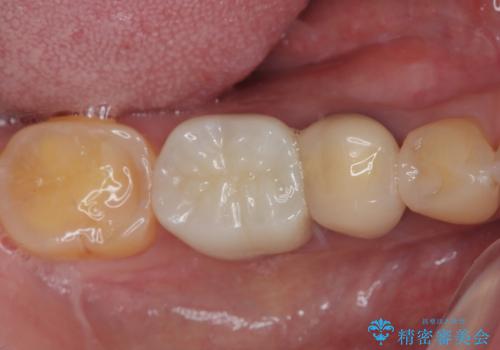

検診で見つかった齲蝕のセラミックインレー修復

齲蝕をしっかりと除去して、精度の高いシリコーンによる型どりを行いセラミックインレーで修復しました。

精度の高い治療は再度齲蝕になるリスクが低いです。